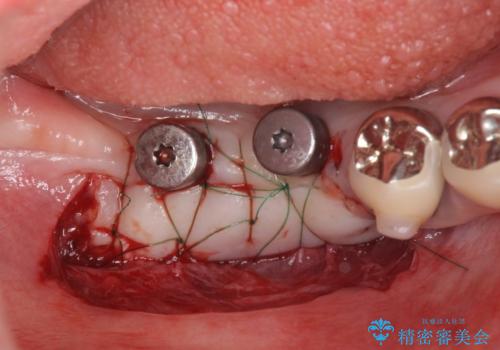

虫歯に伴い歯槽骨の吸収も見られたので造骨後、インプラントを用いて咬合機能を回復します。

また、機能後のインプラント周囲の清掃性を高めるため遊離歯肉移植術を行っています。

- 110万円(インプラント×2・チタンカスタムアバットメント×2・ジルコニアクラウン×2・仮歯×2・遊離歯肉移植術)費用は治療当時の料金となります

遊離歯肉移植術について

インプラント周囲に強固な歯ぐきを移植することで、歯ブラシがしやすくなりインプラント周囲炎対策となります。